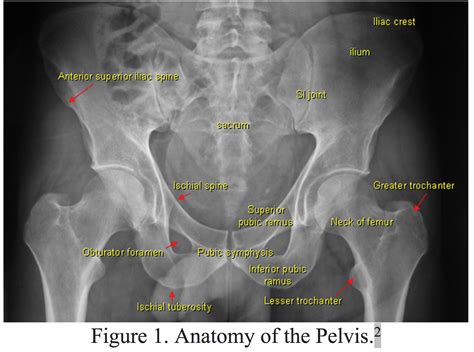

Understanding the Pelvic Anatomy

The pelvis is a ring-shaped structure composed of several bones, including the ilium, ischium, and pubis. The pubic rami are the lower parts of the pubis bones that extend forward and downward from the pubic symphysis, the joint where the two pubic bones meet. These bones play a vital role in supporting the pelvic organs and providing attachment points for various muscles and ligaments.